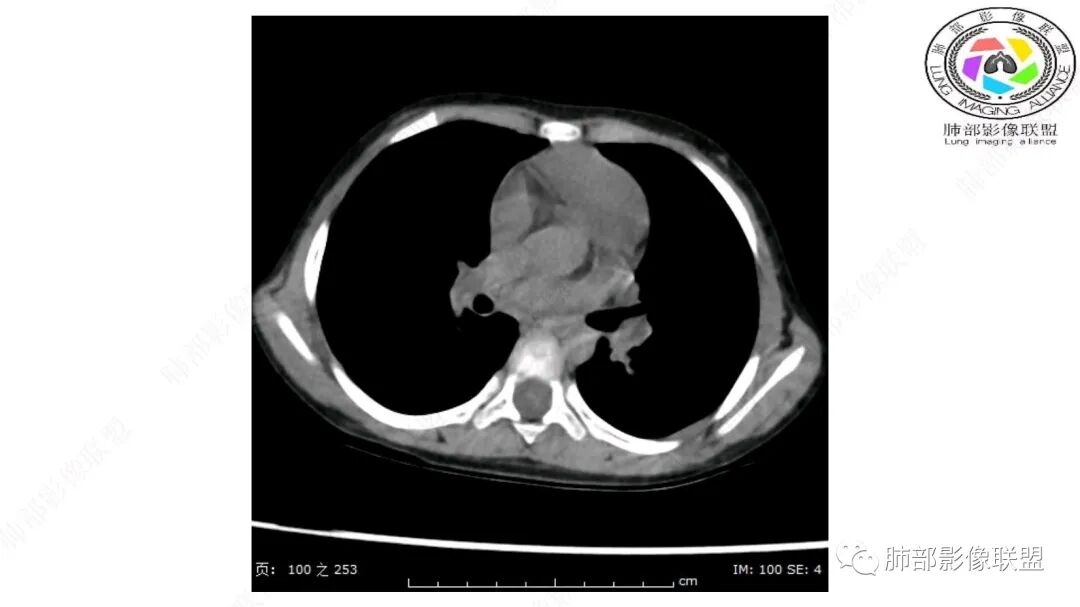

第一个问题:定位:肺内?纵隔?

病灶属于交界区,主体位于肺内,占位效应明显,前方突入胸壁,胸腺受压变形,胸膜显示欠清楚;病灶包绕上叶肺动脉;似乎有体动脉供血。符合肺内的点:包绕上叶肺动脉分支;符合纵隔的点:前方似乎突入胸壁,与胸腺关系比较密切,但是与上腔静脉的关系提示病灶不支持纵隔来源,前纵隔的常规会将上腔静脉受压后移、外移,这是不符合的。

从这个角度符合肺内的,有一点不太踏实的是:似乎突入前胸壁。

手术记录:见右肺上叶肿物,肿物与右肺上叶关系密切。与纵隔无粘连,逐步分离肿物,见肿物大小约6cm*5cm,边界清楚,于右肺上叶粘连,边界清楚,肿物包绕右肺上叶血管及支气管。超声刀逐步游离肿物,完整切除肿物,右肺上叶肺组织无破溃,表面无出血。

1.右上肺-纵隔交界区巨块影,主体位于右肺一侧,紧贴胸腺、头臂干、右锁骨下动脉、上腔静脉、奇静脉等,不能分离,但病灶整体边界清楚。注意上述相邻腔静脉等结构未见受压变形,纵隔亦未见明显向左推移,至少提示两点:

2.肺动脉穿行也许是肺内来源最重要支持点!